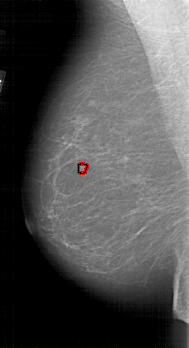

A_1812_1.RIGHT_CC

RIGHT_CC LINES 5491 PIXELS_PER_LINE 2986 BITS_PER_PIXEL 12 RESOLUTION 43.5 NON_OVERLAY

FILE: A_1812_1.LEFT_CC.OVERLAY

TOTAL_ABNORMALITIES 1

ABNORMALITY 1

LESION_TYPE MASS SHAPE LOBULATED MARGINS MICROLOBULATED

ASSESSMENT 4

SUBTLETY 3

PATHOLOGY BENIGN

TOTAL_OUTLINES 1

BOUNDARY